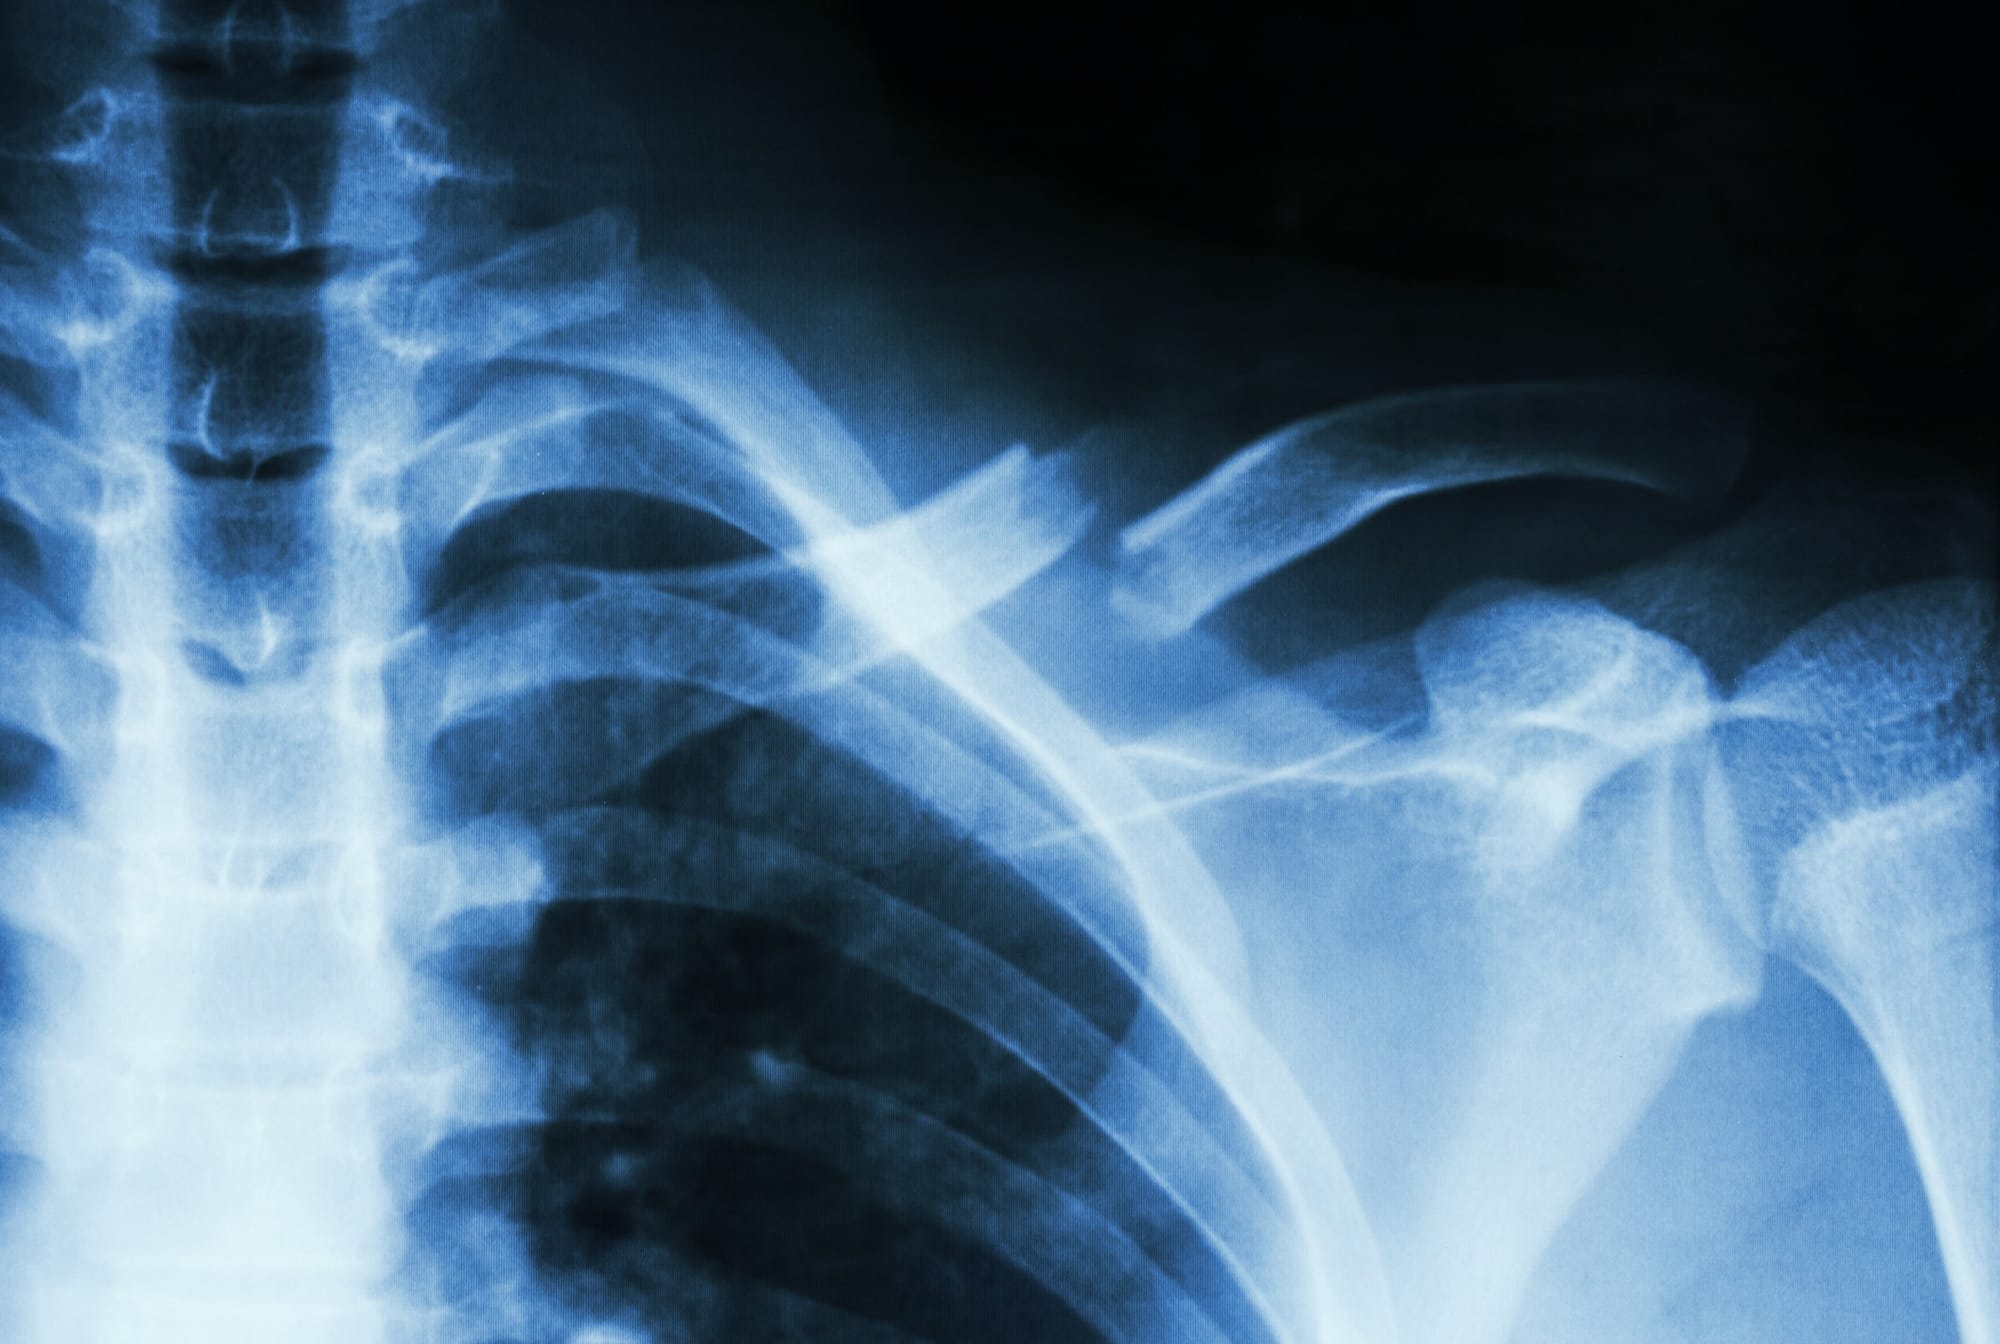

Photo: iStock/Getty Images Plus